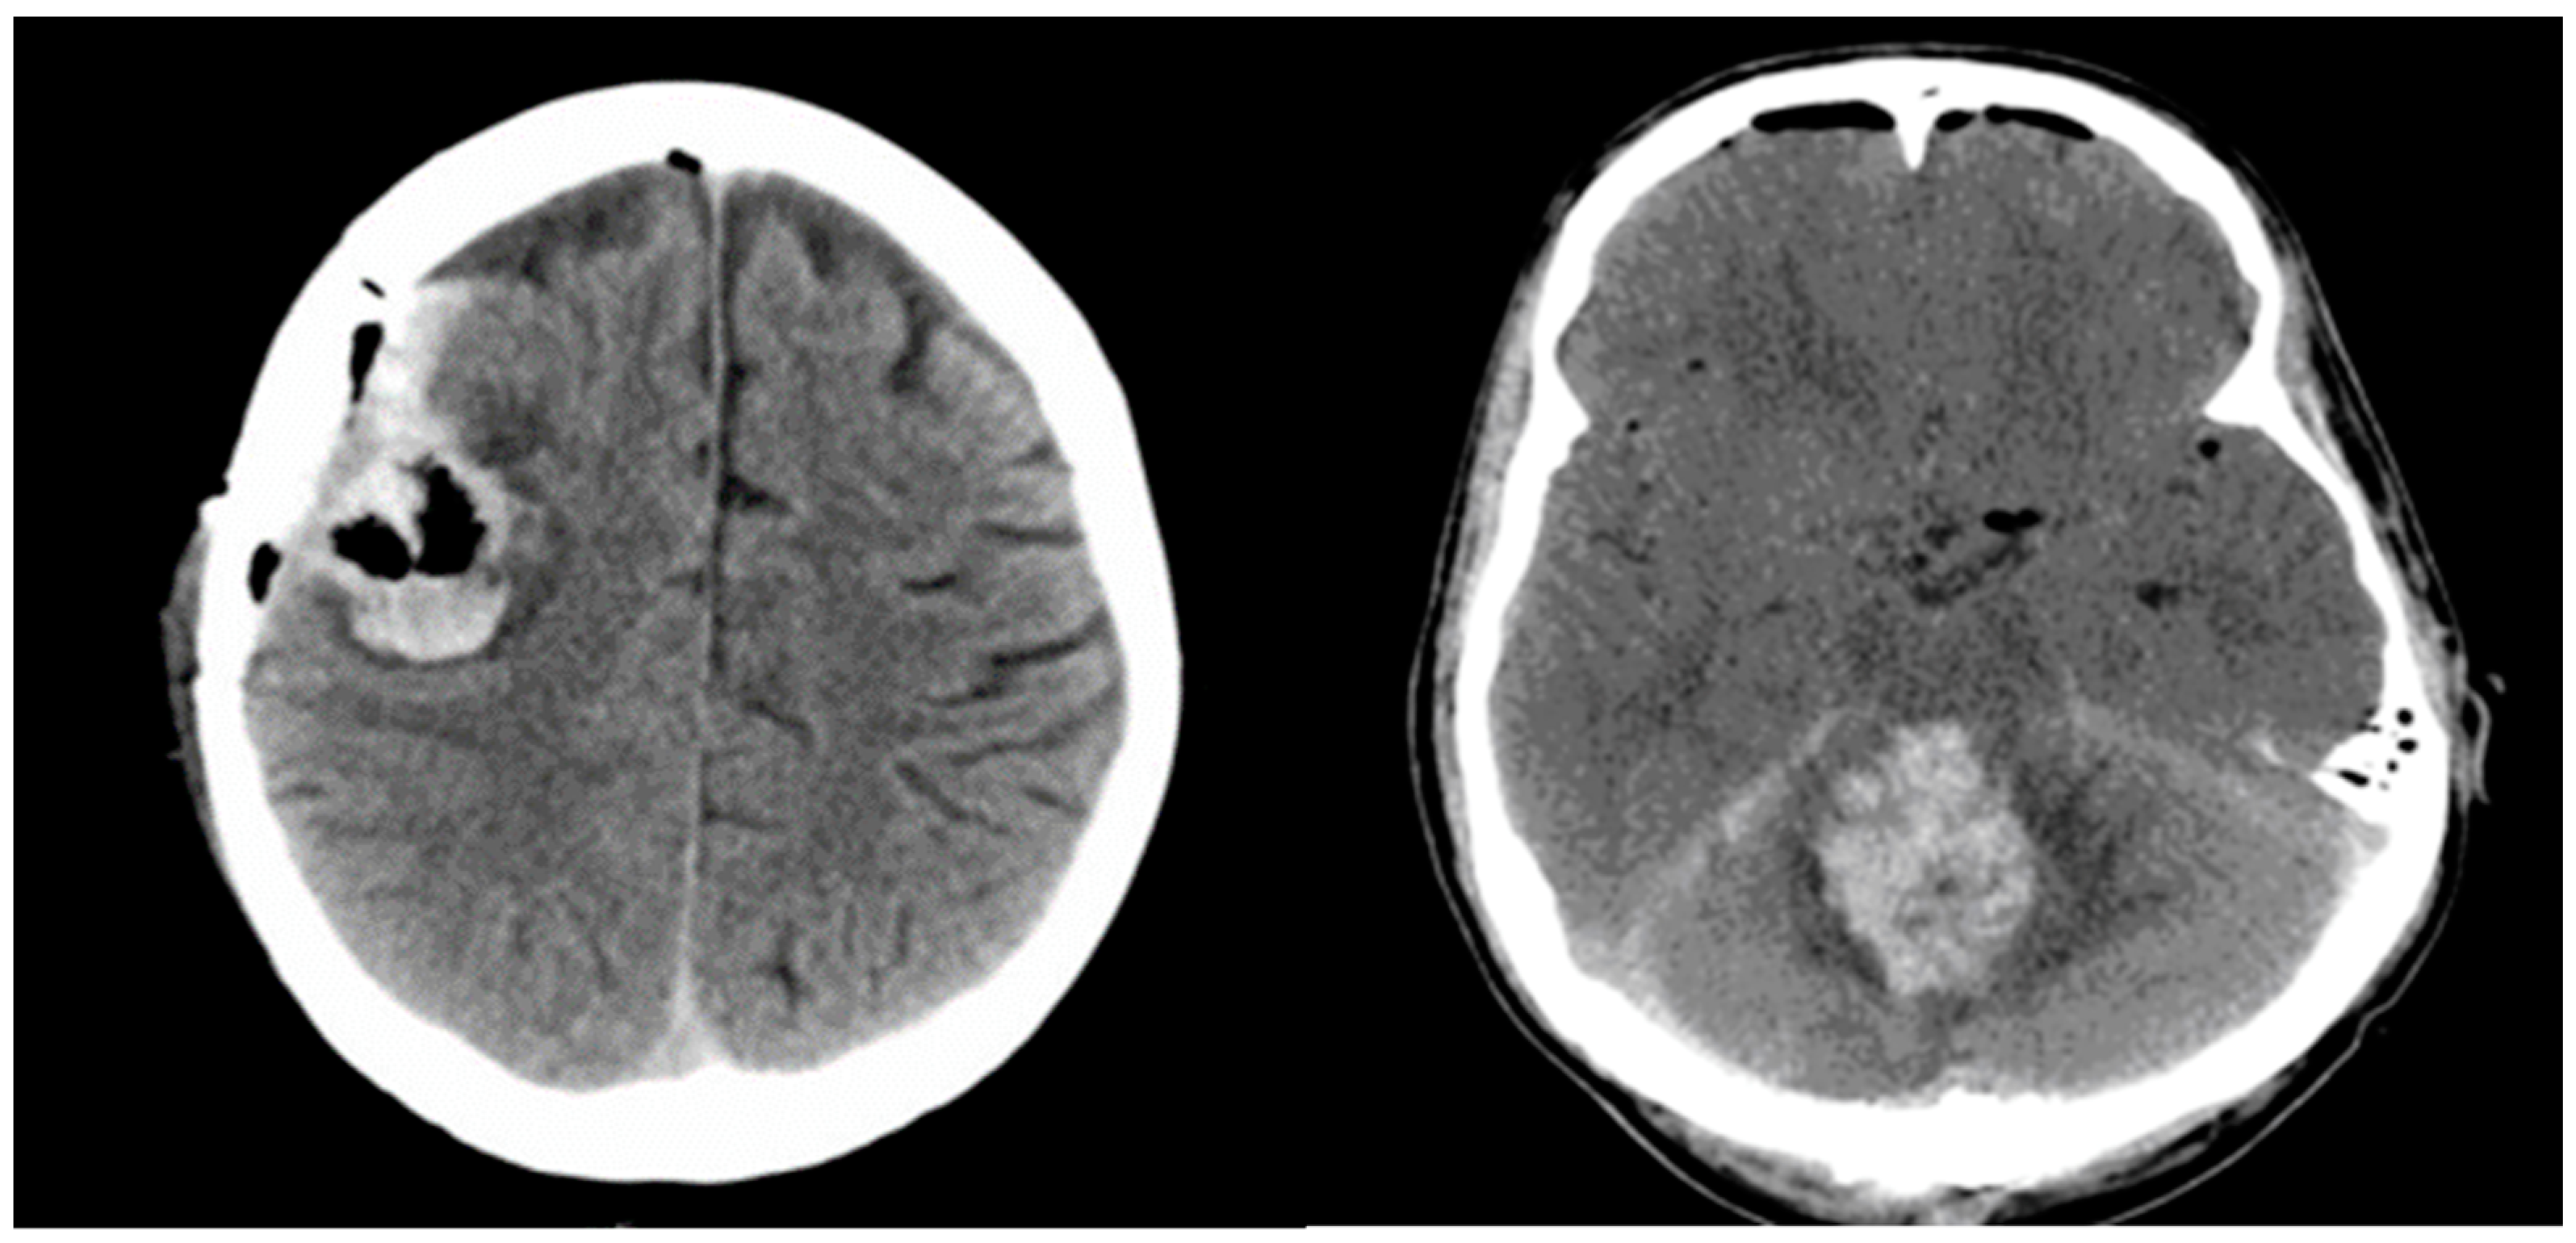

Significant postoperative hemorrhage was defined as bleeding that led to notable neurological symptoms, such as increasing intracranial pressure and space-occupying effects requiring surgical intervention. Symptomatic neurological deficits included focal neurological deficits, headaches, vomiting/nausea, or changes in cognitive function. Figure 2 illustrates two cases of postoperative hemorrhage that required reoperation.

Figure 2. Illustrates two cases of postoperative hemorrhage that required reoperation.